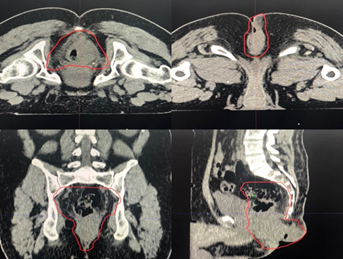

In his assessment, he found significant proctalgia, inability to sit, constipation, and constant bleeding. He received a hypofractionated regimen of 25 Gy in 5 fractions, after which he showed adequate response to treatment with the involution of the exophytic tumor located in the perianal region, decreased pain, and rectal bleeding.

On July 20, 2020, PET-CT was performed without data on tumor activity in the rectal region or other areas with increased metabolism. Even on the day of the delivery of this work, the patient continues to be free of disease. (Figure 4)

Figure 4 Simulation Tomography for planning treatment with Radiotherapy, in the prone position, showing a lesion dependent on the rectal wall, with the extension of 6 cm, towards the anal canal and right gluteus.